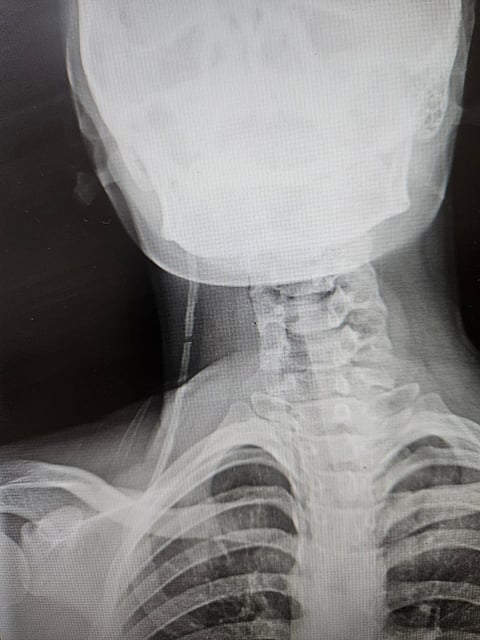

وفي التفاصيل، دخلت الفتاة إلى قسم الطوارئ وتم على الفور استقبال الحالة وإجراء الأشعة والفحوصات اللازمة التي أظهرت وجود زيادة مفاجئة في ضغط المخ مع ارتشاحات بعصب العين؛ نتجت عن قطعٍ وانسدادٍ في الصمام المخي البريتوني الذي تم تركيبه منذ شهرٍ واحدٍ بعد الولادة.

وقرّر الفريق الطبي إجراء جراحة عاجلة استغرقت ساعة ونصف الساعة، تم خلالها رفع الصمام القديم وتركيب صمام مخي بريتوني جديد تكللت بالنجاح دون وجود مضاعفات، ولله الحمد.